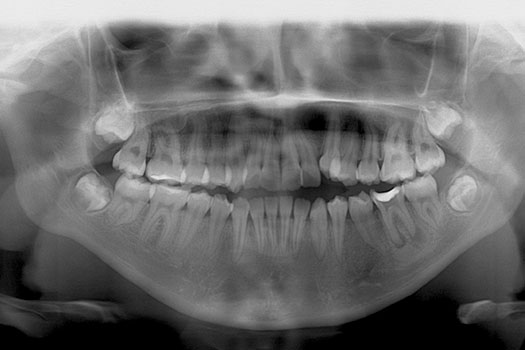

PANORÁMICA

Esta radiografía da una vista panorámica de todos los dientes, es un estudio que se debe hacer de rutina para comenzar cualquier procedimiento en odontología, así mismo el odontólogo la debe solicitar obligadamente a los 6 años de edad para revisar como vendrá el recambio dental, a los 12 años para verificar el recambio dental y a los 18 años para revisar los terceros molares (muelas del juicio), las cuales dan muchos inconvenientes a futuro por falta de espacio y mala posición. De igual manera este estudio permitirá ver patologías en los huesos maxilares, tamaño de raíces dentales, nivel de hueso en el que están soportados los dientes.